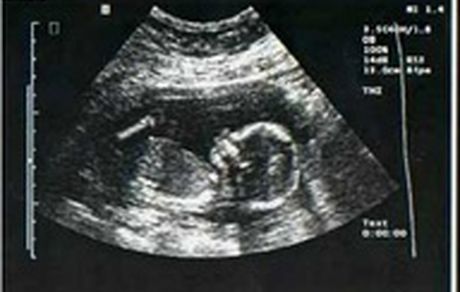

مدیرکل دفتر سلامت جمعیت، خانواده و مدارس وزارت بهداشت درباره نامه ای با عنوان "حذف غربالگری جنین از سامانه های…